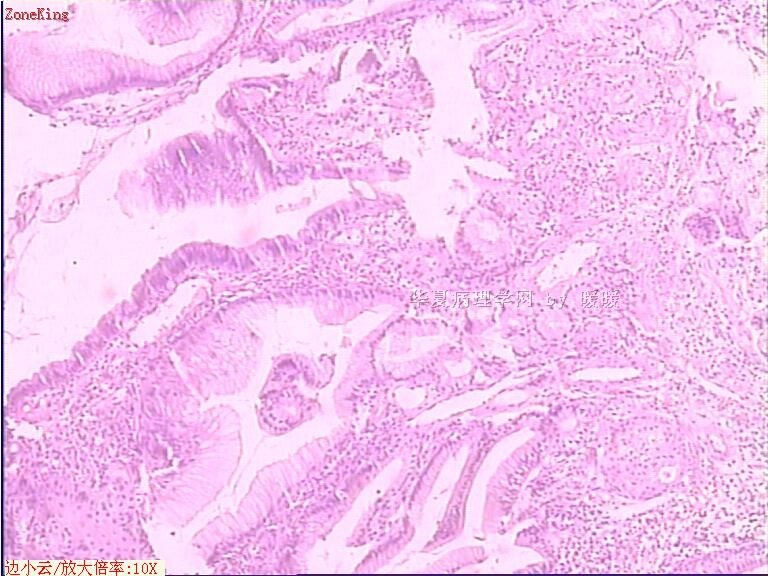

贲门息肉?

姓    名: ××× 性别:  女 年龄:  53

简要病史:  胃镜见,食道下段齿状线上可见一圆形隆起,有蒂,表面光滑,大小0.5X0.5X0.3cm.

各位老师,胃粘膜处出现的鳞状上皮有问题么?

• 贲门息肉?图1

图1

正好是齿状线腺鳞交界处粘膜

鳞状上皮没大问题,可能受炎症影响,稍有增生.

本帖最后由 于 2009-11-21 09:51:00 编辑   谢谢各位老师指点,最终诊断为:贲门慢性炎症,伴局灶细胞轻度异型增生。